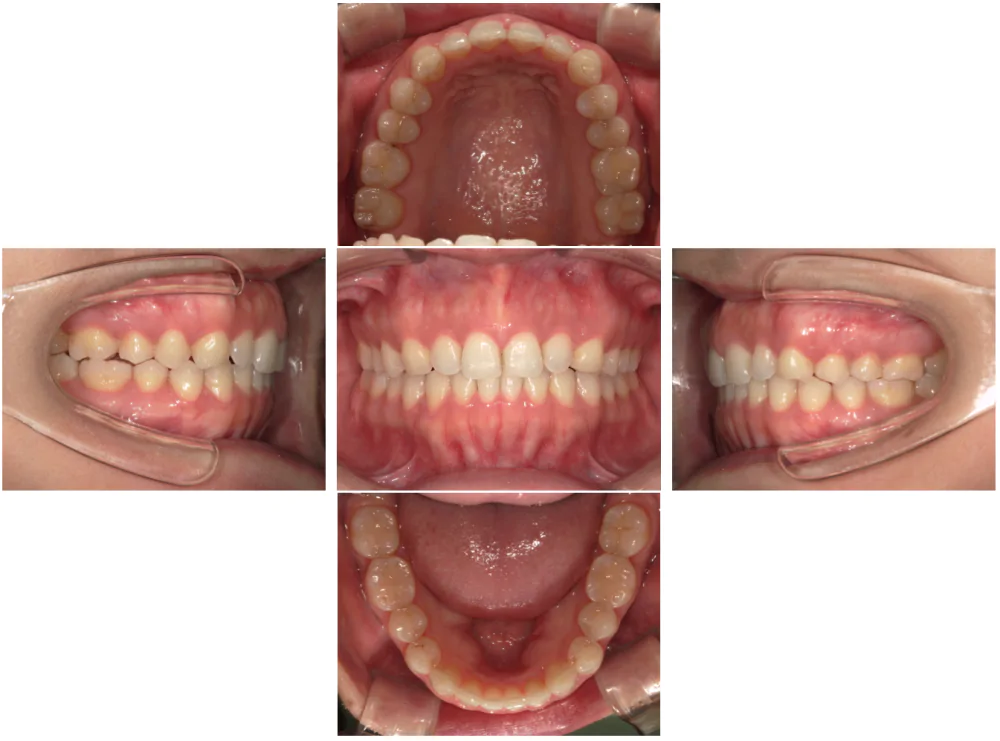

症例3

| 来院時の主訴 | 歯の間の隙間を閉じたい |

| 医院での対応や適用装置 | マウスピース矯正装置を使用して主訴である歯の間の隙間を閉じて改善を行いました。 歯の隙間の原因は飲み込み時に舌を前に出してしまう癖だと考えられましたので、 トレーニングを行い癖も無くなりました。 |

| 通院期間 | 6ヶ月 |

| 通院回数 | 5回 |

| 治療費用総額 | 577,500円(税込) |

| リスクと副作用 | 矯正治療による歯の移動に伴う痛み、歯根吸収、虫歯 |